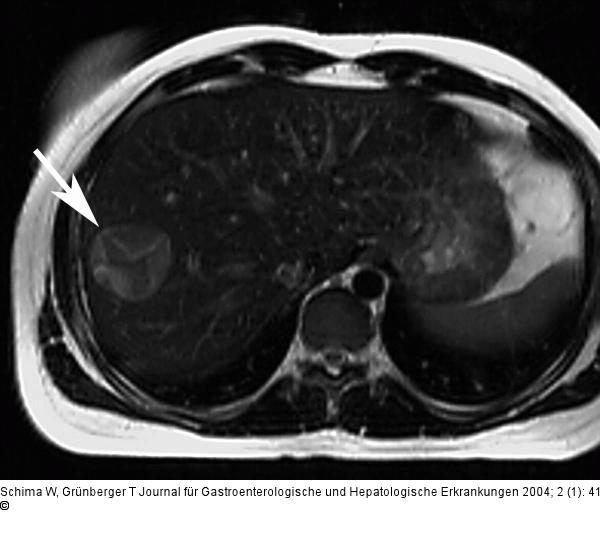

Aktuelle Bilder: Echinokokkus der Leber

Abbildung 2: Echinokokkus - Leber